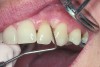

The presence of keratinized tissue around teeth and implants and its role in periodontal maintenance is somewhat controversial. It has been suggested that 2 mm of keratinized tissue is important to maintain gingival health around teeth.16 Minimal recession also facilitates maintenance by the therapist and plaque control by the patient (Figure 4 and Figure 5). Keratinized tissue around implants is also important. Chung et al17 completed a retrospective study examining the barrier function of keratinized tissue around dental implants. They examined 339 endosseous dental implants in place for at least 3 years in 69 patients and found that when an adequate band of keratinized tissue was present, less inflammation and plaque accumulation occurred (Figure 6 and Figure 7). Although there was no correlation to bone loss, there was improved comfort while cleaning the sites with keratinized tissue versus those areas that lacked keratinized tissue.

Geurs et al18 also found that establishing a soft-tissue barrier sheltered the underlying osseous structures and the osseointegration around the implant body. Kim et al19 conducted a study with 276 implants placed in 100 patients and demonstrated that cases with insufficient keratinized gingiva near the implants showed increased risk of gingival recession (Figure 8) and crestal bone loss. It is critical that keratinized tissue be evaluated around both teeth and implants, and when there is an insufficient amount, treatment should be considered to increase the thickness and overall health.

Fig 7. Close-up view of the No. 23 implant-supported restoration showing inflammation surrounding the site (this area had not been grafted).

Figure 7

Fig 8. The implant on No. 23 4 years later with no maintenance care, showing increased inflammation and recession.

Figure 8